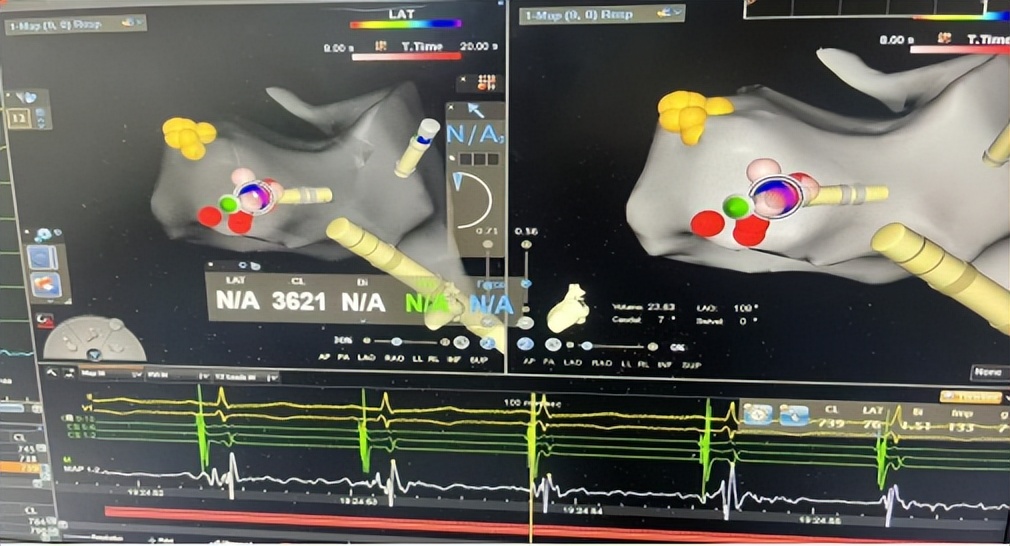

手术的关键,是找到心脏里的“异常激动点”。郑全主任团队通过股动脉送入射频导管,在三维导航仪指引下,在心脏主动脉瓣二尖瓣连接处(AMC区域)精准定位。

△术中三维导航,确定异常病灶,治疗快速性心律失常